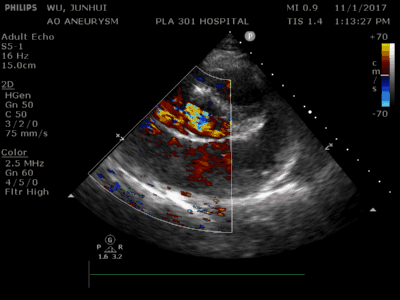

肺动脉瓣轻-中度反流左心扩大主动脉无冠窦破裂印象:肺动脉瓣轻-中度

多次行心脏超声检查,提示升主动脉增宽(40~42 mm),左心扩大,左心室室